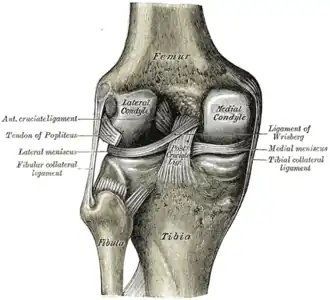

Левый коленный сустав сзади, показаны внутренние связки. | |

Крестообразные связки. Передний и латеральный вид колена.

Передний и латеральный вид колена.